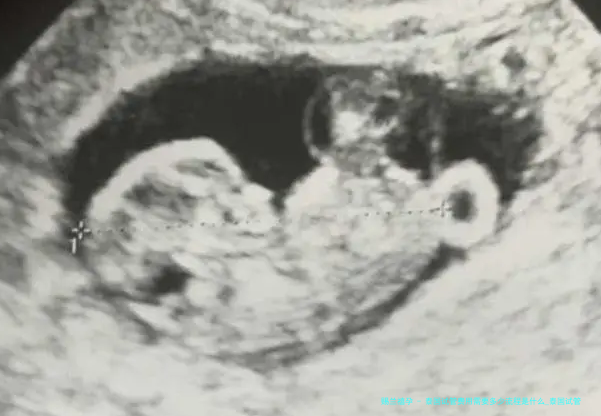

二、固然在受孕卵发育成熟后快要移植到母亲的子宫殿里;子宫里进行怀孕,在一般情况下就会成功受孕,如此就能期待十个月,然后进行临盆了,在怀孕的过程当中也要注意饮食情况以及歇息的情况,预防出现一些隐患影响到胚胎的发育,并且每个月都打算去医院进行检查胚胎是否是发育正常。